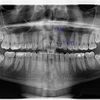

ألم الأسنان

تسوس الأسنان

نقص الأسنان

نزيف اللثة

صرير الأسنان

اعوجاج الأسنان

أمراض الأسنان واللثة

التهاب ما حول الزرعة

التهاب مخاطية ما حول الزرعة

نقص نمو منطقة الأسنان والفك والوجه

أكياس الفك

تطبيقات الزركونيوم

علاج الزرعات

تطبيقات البورسلين

فينير القشرة التجميلية